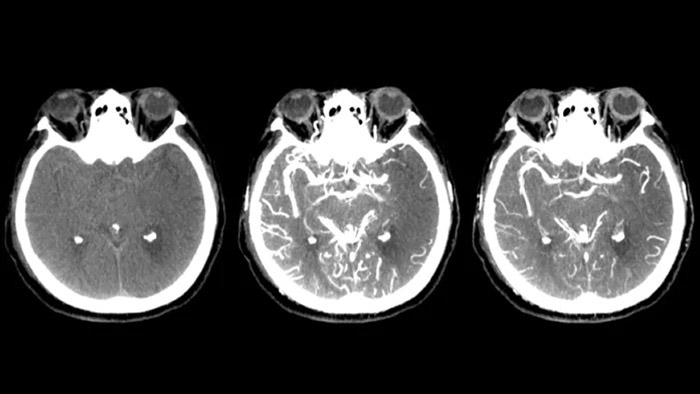

Visualisation de type TDM

SmartCT Soft Tissue  génère une visualisation des tissus mous de type TDM et prend en charge le diagnostic des AVC de trois façons. Une acquisition sans produit de contraste facilite la détection des changements ischémiques précoces. Une acquisition en phase précoce permet d’identifier l’occlusion proximale. Une acquisition avec agent de contraste en phase tardive prend en charge la détection des collatérales.